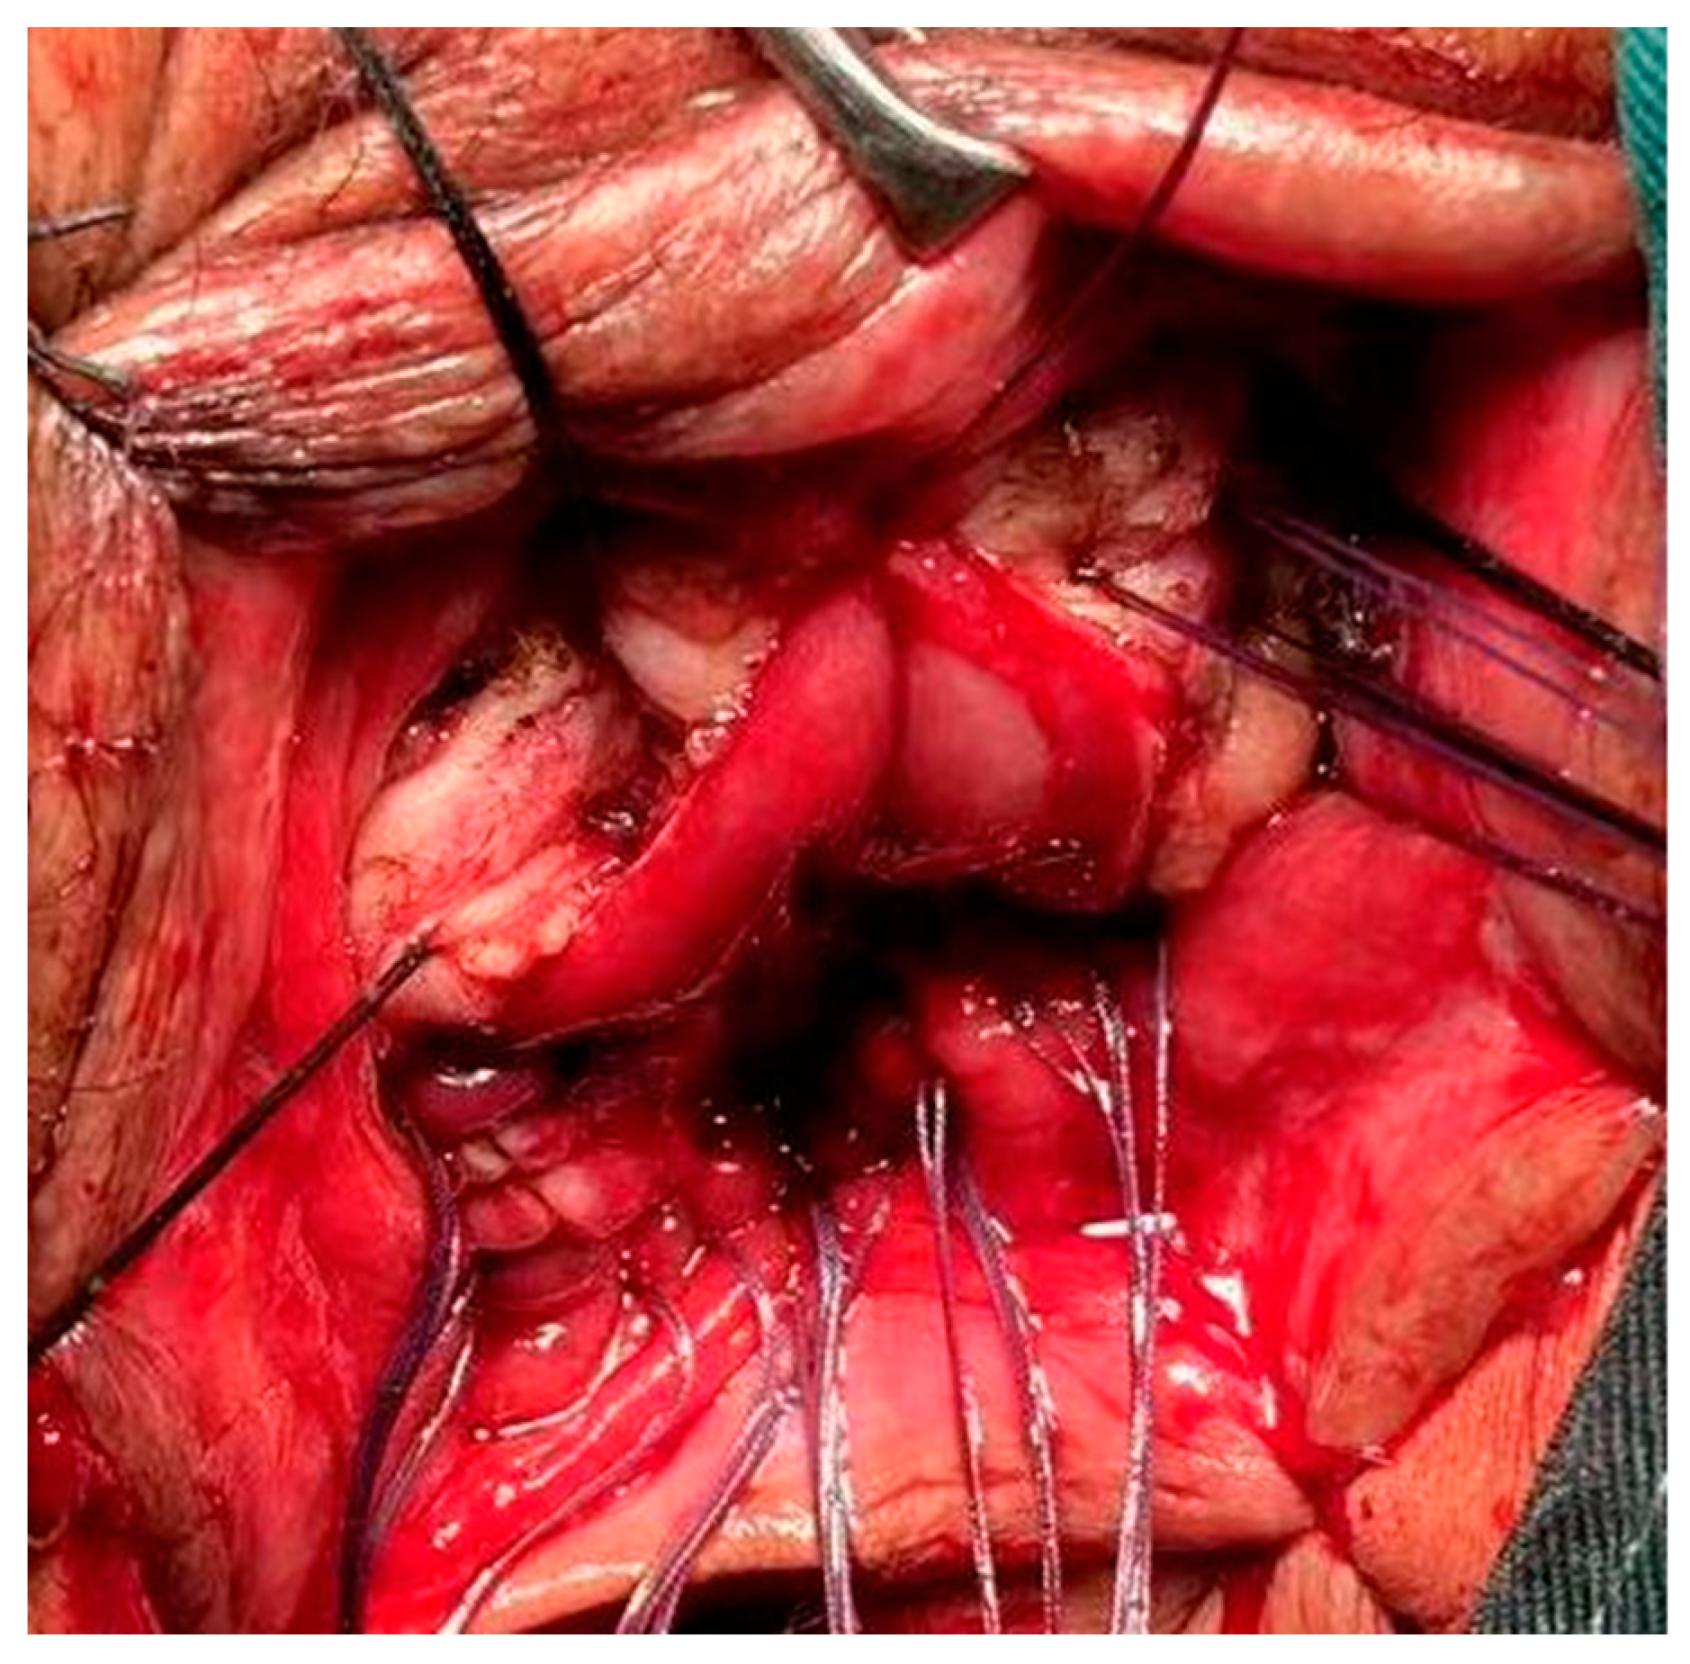

Figure 5. Surgically resected rectal prolapse specimen. The anatomical defect of pathological dilatation of the distal rectum was presented in the surgical specimen.

After intraoperative resection of the specimen, the distal and proximal diameters were measured using a specimen measuring tape to determine the distal and proximal diameters. (Figure 5)

In their long-term clinical practice, the authors found that patients with CRP may have a drastic change in diameter at the site of intestinal lumen ligature, an anatomical abnormality that has not yet been reported. The weakness of the distal bowel wall at the site of ligature results in poor resistance to high abdominal pressure during defecation, and conventional Altemeier surgery that does not completely correct the difference in bowel lumen diameter may lead to re-ligature and recurrence of CRP. To improve the above anatomical abnormalities, a modified Altemeier procedure is described in the present study. In this study, we performed either conventional Altemeier or modified Altemeier surgery in the 60 patients with CRP included, and summarized and analyzed the clinical outcomes. We hypothesized that the surgical efficacy of modified Altemeier surgery for CRP was superior to that of conventional Altemeier surgery. Through this retrospective analysis, we compared the clinical indicators of recurrence rate, complication rate, postoperative anal function and quality of life between conventional and modified Altemeier surgery to verify our hypothesis and provide a reference for the selection of surgical modality for CRP patients.